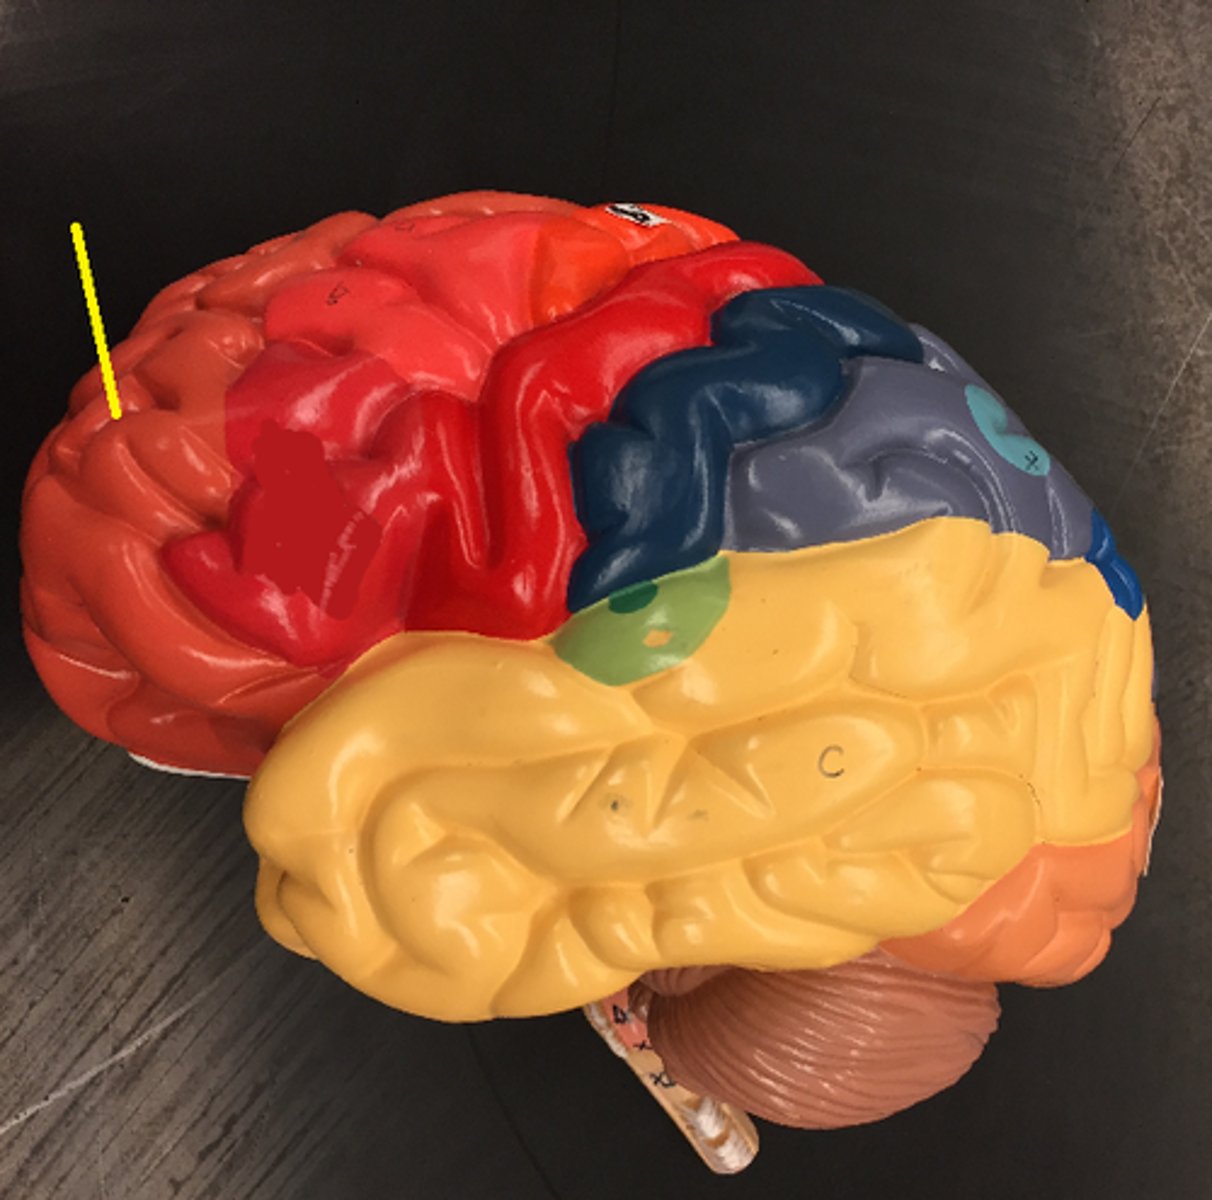

central sulcus

lateral sulcus

frontal lobe

temporal lobe

parietal lobe

occipital lobe

Broca's area

Prefrontal cortex

Premotor cortex

Wernicke's area

Primary visual cortex

Primary auditory cortex